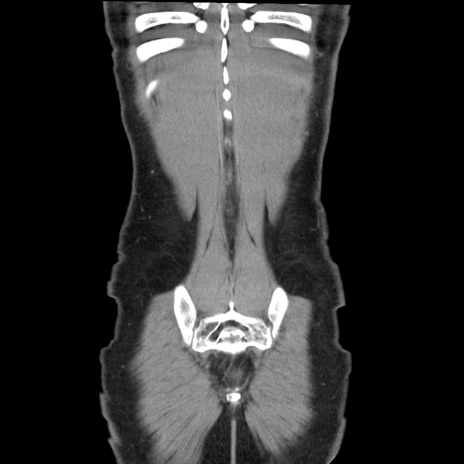

症例36(冠状断像)

【症例】20歳代 男性

【主訴】心窩部痛

【現病歴】今朝より上腹部痛あり。一旦軽快していたが再度出現したため救急要請。昨日夕に白身の魚を含む刺身を食べた。

【身体所見】BP 136/89mmHg、HR 74/min、BT 37.0℃、腹部:膨満、軟、心窩部に圧痛あり。反跳痛なし、筋性防御なし、腸雑音やや亢進あり。

【データ】WBC 17700、CRP 0.48

横断像